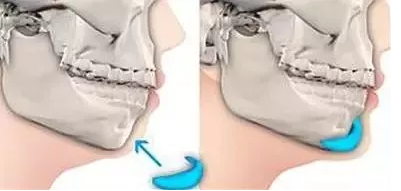

假体植入丰下巴

假体植入采用口内做微小的切口,根据求美者颏部的情况选择合适的医用固体-硅胶或者膨体假体进行雕刻,然后将雕刻好的假体植入骨膜下并将其缝合固定,恢复后无疤痕。

优点:现在假体材料技术成熟,生物相容性好。选择和人体相容性好的硅胶或膨体假体,塑造性好。